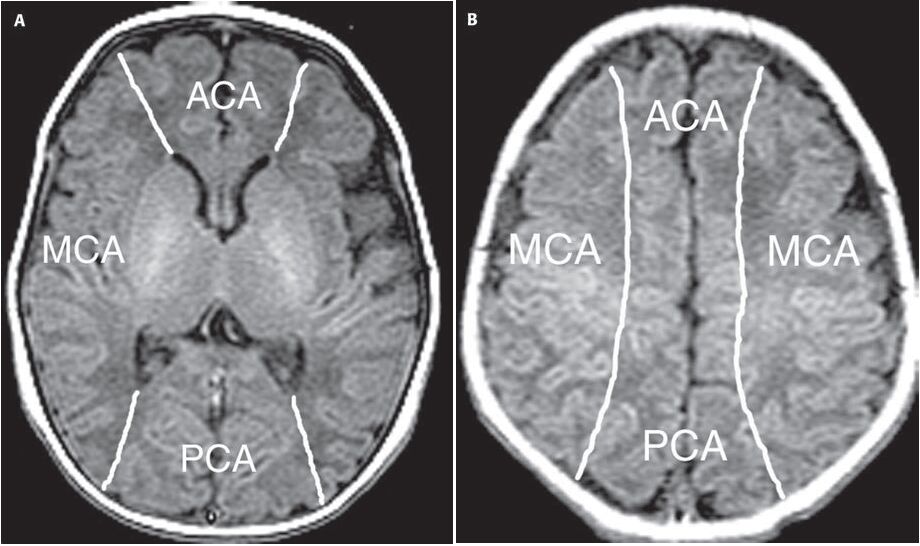

(B) 前大腦動脈梗塞型中風

(C) 中大腦動脈梗塞型中風

ACA、MCA、PCA的範圍如圖: